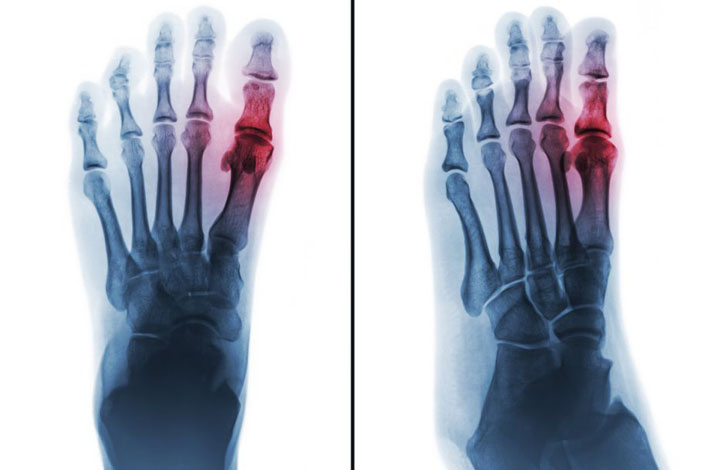

Dna stawowa wynika z odkładania się kryształków moczanu sodu w błonie maziowej stawów i innych tkankach w wyniku przesycenia płynu zewnątrzkomórkowego kwasem moczowym. Manifestacją tej choroby jest hiperurykemia, definiowana jako stężenie moczanu (kwasu moczowego) w surowicy wyższe niż 6,8 mg/dl (402 mmol/l). Jest ona stwierdzana u 21% dorosłych Amerykanów, a ilość kwasu moczowego wzrasta z wiekiem u mężczyzn i po menopauzie u kobiet. Na wystąpienie hiperurykemii istotny wpływ wywiera otyłość, dieta bogata w mięso i owoce morza, słodzone napoje i alkohole (zwłaszcza piwo i wino), unikanie mleka i jego przetworów, a także leki zmniejszające wydalanie moczanów przez nerki (cyklosporyna, takrolimus, kardiologiczne dawki aspiryny, tiazydy). Jest ona częstym objawem u chorych na niewydolność nerek, niezależnym czynnikiem prognostycznym wystąpienia nadciśnienia i choroby sercowo-naczyniowej, niewydolności serca, udaru i choroby nerek. Przewlekłe odkładanie się kryształków w stawie, które można zobrazować na powierzchni chrząstki artroskopią, ultrasonografią lub rezonansem magnetycznym, prowadzi ostatecznie do rozwoju pełnoobjawowej dny (1). Częstość występowania dny jest oceniana na 3,9% w USA, 0,9% we Francji, 1,4–2,5% w Wielkiej Brytanii i 1,4% w Niemczech i stale wzrasta (2,3).

Zdjęcie: Photogenica.